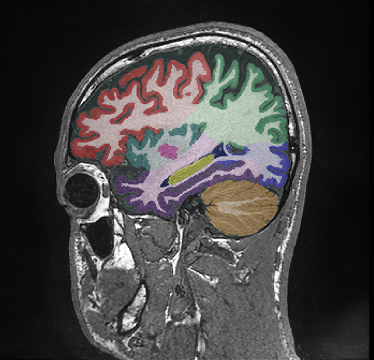

Retrospective brain volumetric analysis in a female patient diagnosed with Alzheimer’s disease at age 77 showed progressive brain atrophy over a 5-year period. The scans demonstrate both hippocampal volume loss and a clear left–right asymmetry.

PATIENT

Female patient diagnosed with Alzheimer's Disease at Age 77

Analysis period

5 years

regions of interest

Hippocampi

Inferior lateral ventricles

Age 72

Age 76

Age 77

Whole brain